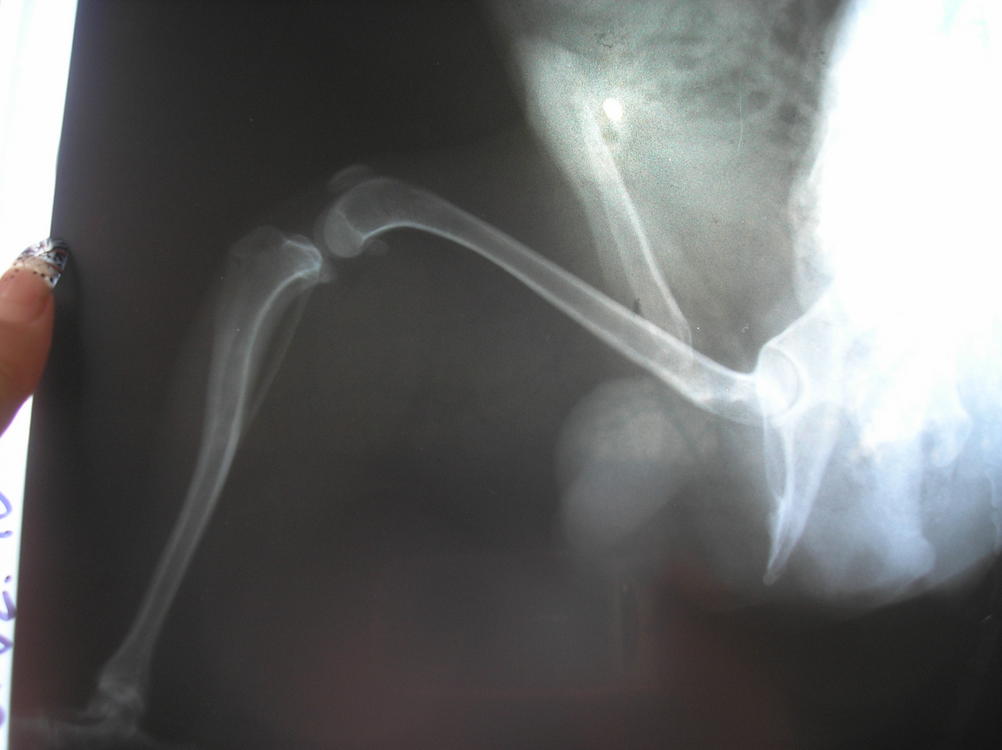

Мы сегодня сделали рентген с анестезией, на правом 2ая степень, на левом нестабильность, т.е. 1ая степень...травматолог говорит нужна операция, день правда еще не назначили...:flushed:

Вот наши результаты:

Я не отказалась, т.к. по этому рентгену даже я увидела все это!(

Плюс его нормально осмотрели (пока под наркозом был), правая коленка совсем болтается и левая тоже нестабильная. Завтра закажут все материалы специально для Тоськи и назначат день. На левой травматолог хочет укрепить связку, чтобы вывиха не было, а правую оперировать по полной! Надеюсь, нам это поможет жить полноценной жизнью, а пока покой-покой-покой!